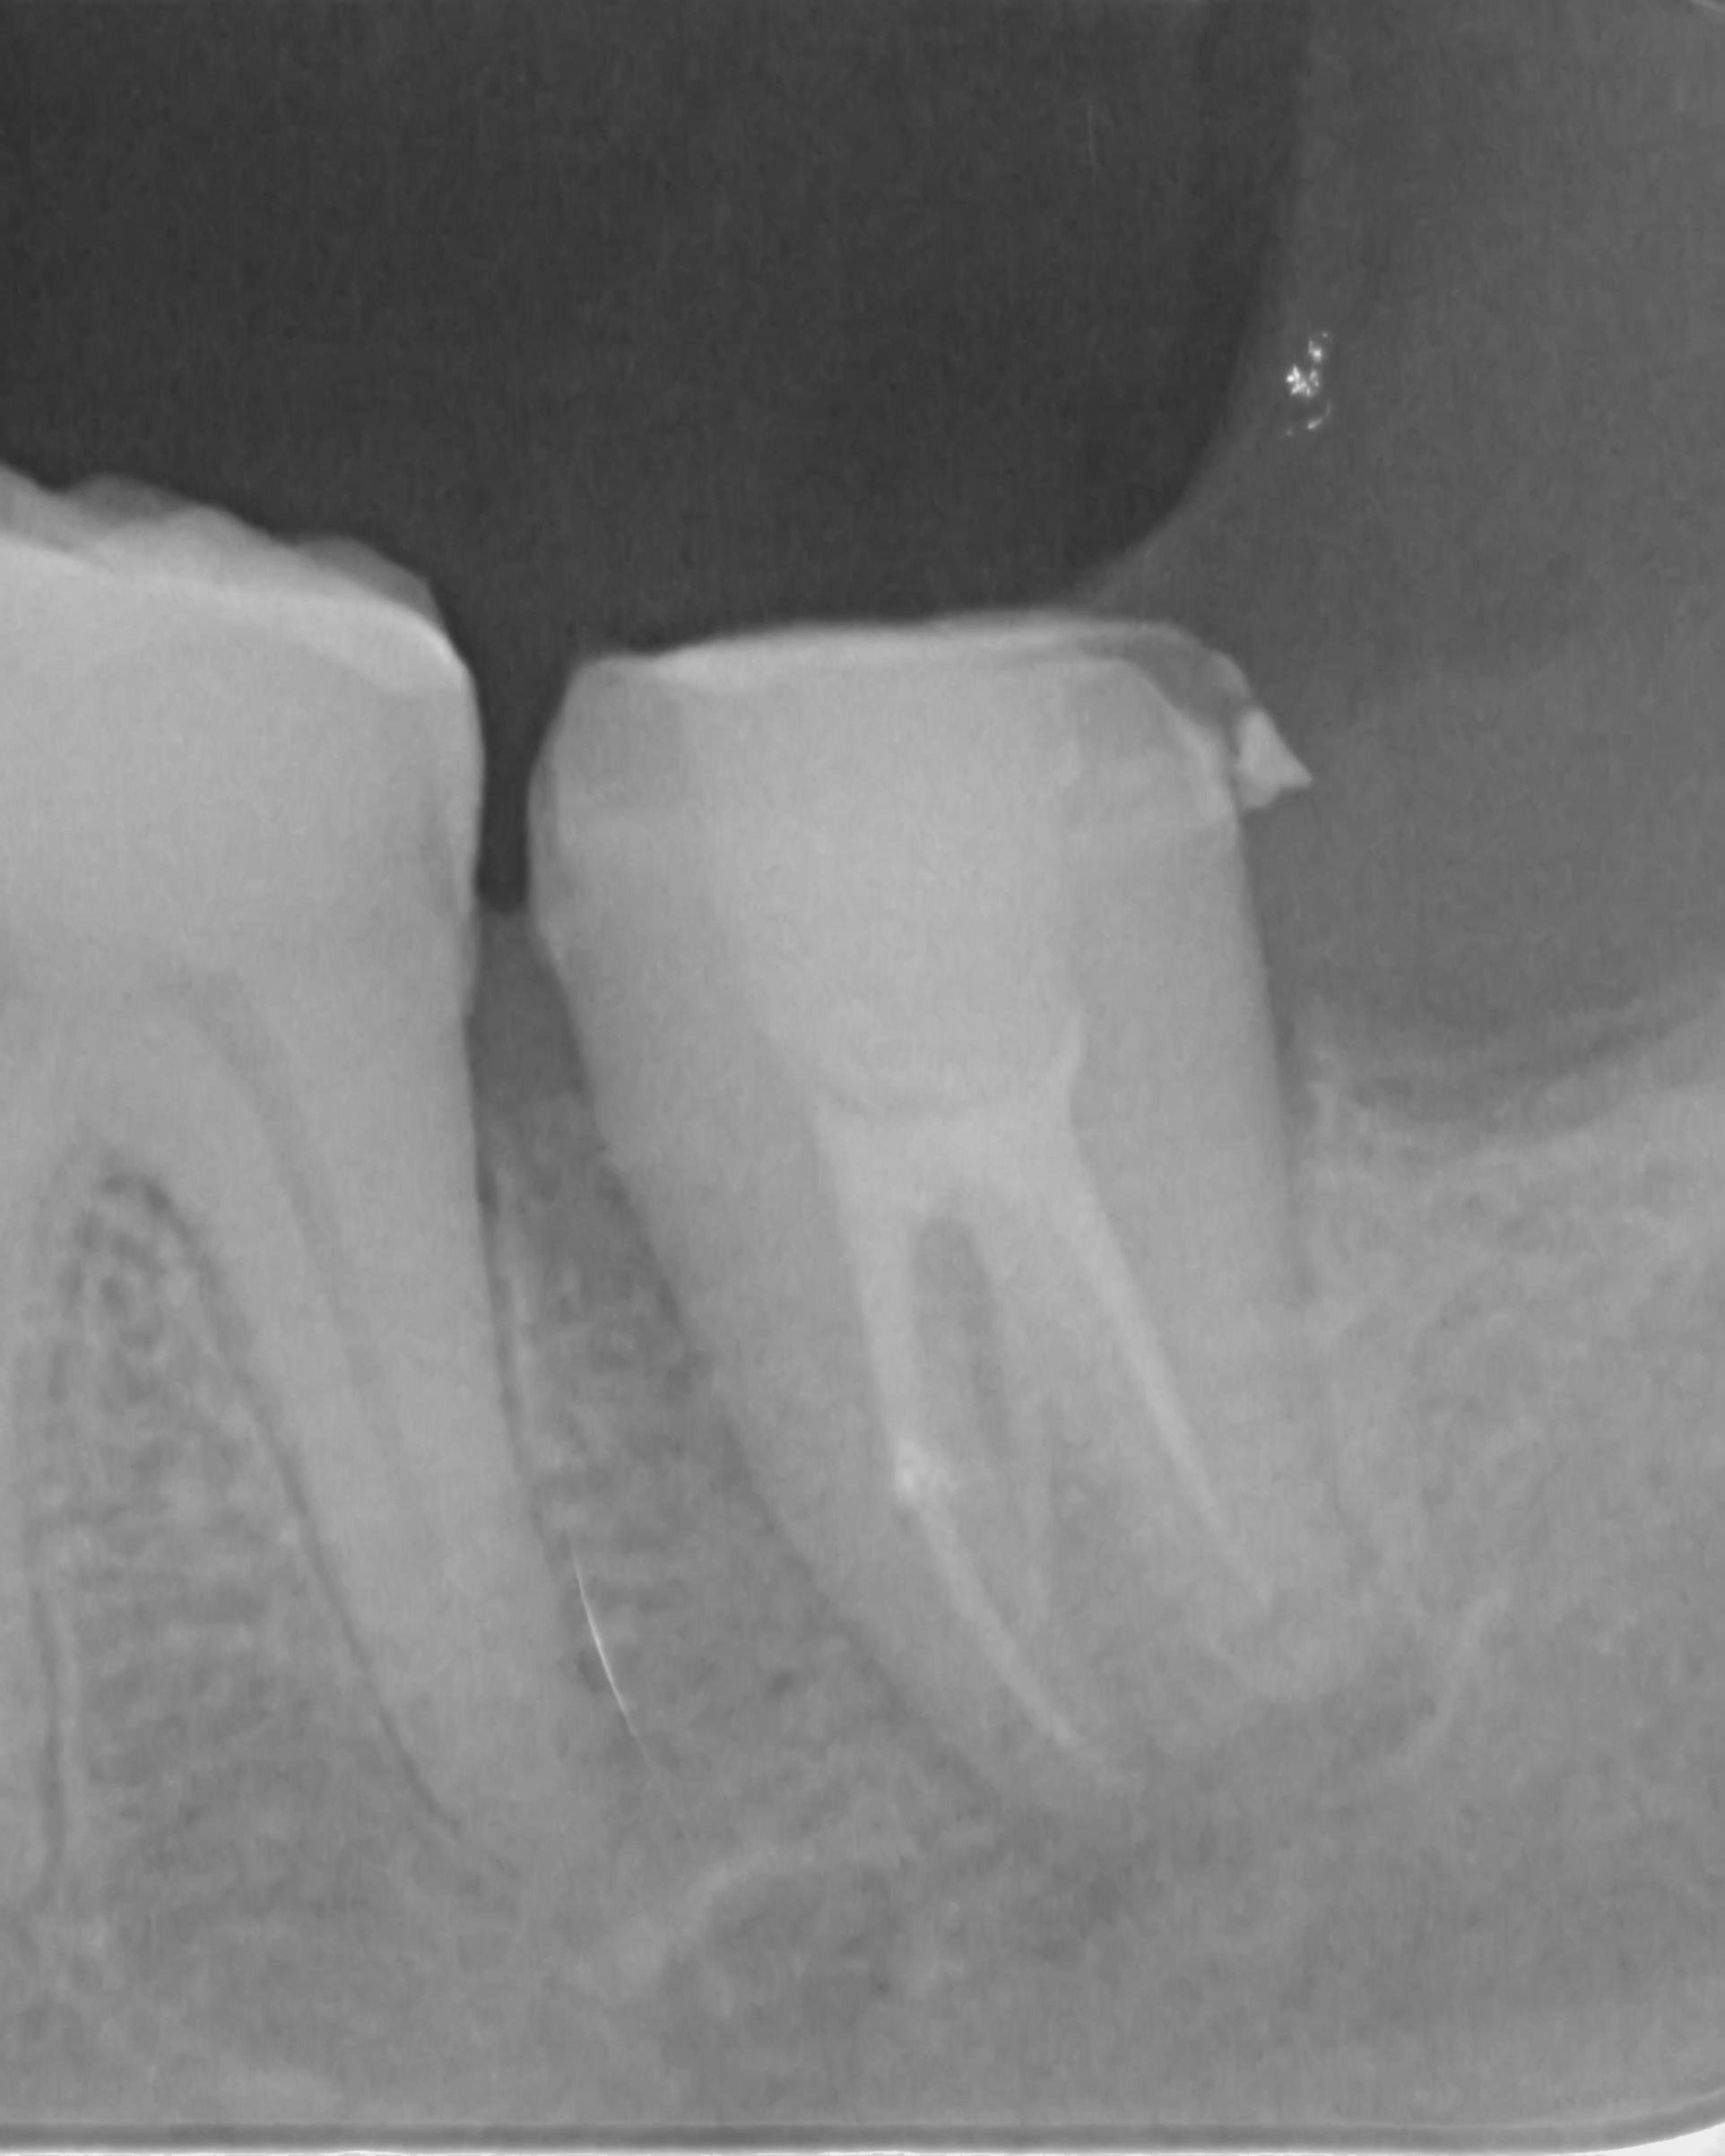

Perawatan saluran akar adalah salah satu perawatan yang berfungsi untuk menghilangkan atau memberhentikan sumber infeksi yang berkembang biak. Sering kali perawatan ini di sebut dengan perawatan saraf atau perawatan syaraf gigi, penggunaan nomenklatur ini dirasa kurang tepat. Tujuan lain dari perawatan saluran akar selain menghilangkan infeksi, perawatan saluran akar bertujuan mempertahankan gigi semaksimal mungkin didalam rongga mulut. Root Canal Treatment or Root Canal Therapy are The process of removing an infected, inflamed, or necrotic pulp and filling the residual space with an inert material. Access must first be gained to the pulp chamber and root canal system; the pulp canals are then measured and the pulp tissue and any infected material removed; the canals are then shaped, irrigated, and cleaned of debris; the root canals are obturated with a root filling material such as gutta-percha and a sealant, and finally a coronal seal placed to prevent bacteria from the mouth entering the root canal system. thank you for eighteeth dental and revoden asia using fast fill and fast pack to fiilling a root canals for more info you can visit my instagram https://www.instagram.com/furqan_rizal/ or contact my clinic +6281219972701